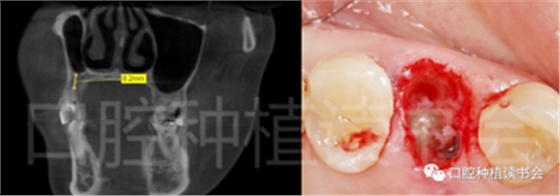

術前CBCT(美亞光電)檢查:47根分叉下方骨高度及骨寬度滿足即刻種植要求(圖13)。

圖13 47根分叉區(qū)骨寬度及骨高度(與下頜神經(jīng)管之間的距離)滿足即刻種植要求。

另外,牙根的長度(根分叉到根尖的長度)將決定安全種植的骨高度或深度,應避免根尖以外的解剖“危險區(qū)”(例如,下牙槽神經(jīng)、上頜竇,圖11)。

圖11 擬行即刻種植的位點術前應CBCT檢查

根分叉距離下頜神經(jīng)管或上頜竇的距離。